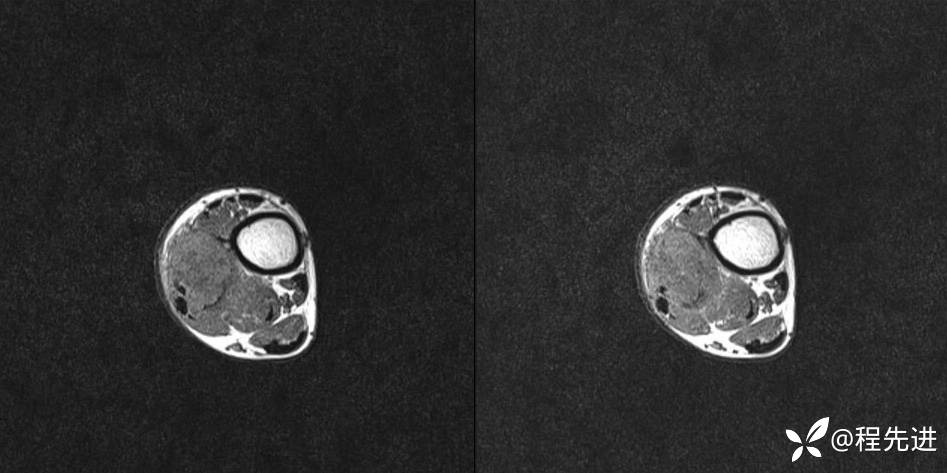

MR

T2

T1